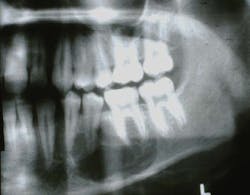

Figure 1: CGCG (Photo courtesy of James J. Sciubba, DMD, PhD)

The CGCG lesion is usually discovered on radiographs (figure 1), appearing as a radiolucent lesion with expanding margins. It appears as a multilocular or a unilocular well-defined radiolucent lesion. CGCG lesions may be confused with periapical cysts, periapical granulomas, and larger growths such as the ameloblastoma. The first indication of the CGCG may be mobility or expansion of teeth. Although most CGCG lesions occur in the mandible, when found in the maxilla, they may invade the sinus floor and the sinus passage, leading to facial asymmetry.2